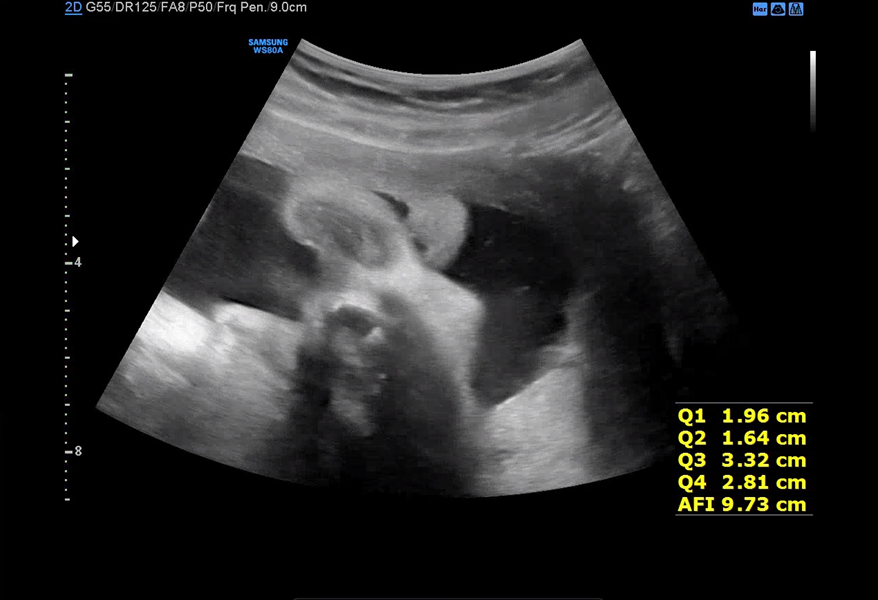

병원에 도착하고 전과 똑같이 소변검사 후 초음파 검사를 했다. 처음엔 배 초음파를 본 뒤 내진을 하신다고 하셔서 옷을 갈아입고 진료 의자에 앉았다. 배 초음파 보는 순서는 늘 똑같은데 BPD, 아기 심박수, FL, AC, 양수 체크를 하신다.

이제 서서히 양수가 줄어든다고 하셨는데 초음파로 봐도 아기가 있을 공간이 좁은게 느껴진다. 아가야 조금만 더 힘내자!

매주 초음파 검진 결과를 열달후에라는 앱에 기록하고 있다. 35주와 37주 태아성장기록이 너무 드라마틱하게 변해서 뭔가 웃기기도 했다. 35주 때는 좀 잘 먹어서 급격히 아기 복부둘레가 늘고 체중도 33주보다 500g이 증가했었는데 이번엔 애기 배가 완전 줄어있었다. 이것이 운동의 효과인가! 초음파 진료 후 첫 내진을 했는데 원장님도 생각보다 좀 더 불편할 수 있다고 말씀하셨지만 생각보단 아무렇지 않았다. 그냥 질초음파 보는 느낌과 거의 유사했다. 자궁이 1cm도 안 열렸다고 아직 딱딱하다고 하셨다. 이러면 예정일보다 훨씬 늦게 나올 수 있어서 배가 좀 뭉칠때까지 많이 걸어야 한다고 해주셨다. 이러다가 유도분만 시도하거나 제왕 할 수도 있다며... 내가 그동안 너무 잘 쉬었나 보다. 지난번 막달 검사 결과로 간단히 알려주셨는데 질 균도 없고 갑상선 수치나 철분 수치 모두 잘 유지되고 있다고 알려주셨다. 이제 38주부터는 언제 출산해도 이상하지 않은 상황이라 출산 가방을 미리 싸둬야 한다. 병원도 일주일마다 진료를 보러 가는데 부디 39주까지 아기가 잘 버텨주었으면 좋겠다. 블로그에 이렇게 기록하는 것도 얼마 남지 않았다. 연말이 지나 새해가 오면 우리 아기가 온다는 얘기라 늘 설레면서도 떨렸는데 요즘은 출산 생각에 뭔가 뒤숭숭하다.